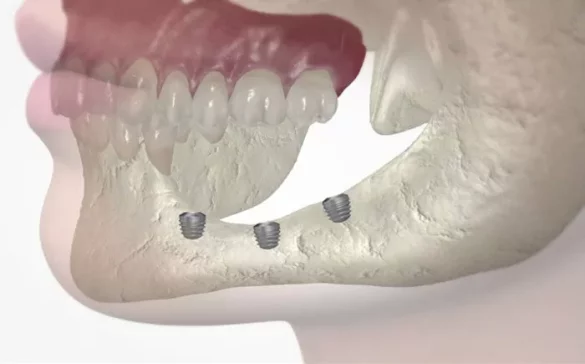

blueSKY Implant: Suitable for most clinical cases, this implant type offers high primary stability and a design optimized for immediate loading protocols. It is especially recommended for aesthetic areas such as the anterior teeth.

narrowSKY Implant: A narrower-diameter version of blueSKY, ideal for lateral incisors or sites with reduced bone volume or narrow interdental spaces. This implant is particularly useful in generally atrophied jaws where bone tissue is compromised.

miniSKY Implant: This is a small-diameter implant designed for prosthesis fixation when reduced implant diameter is required, such as in cases with limited bone width.

copaSKY Implant: Designed specifically to address biomechanical challenges and provide excellent integration with surrounding tissues, widely used in both single-tooth and full-arch restorations.

These implant types enable clinicians to restore single teeth, multiple teeth, or even fully edentulous arches. Applications include replacement of teeth lost due to trauma, decay, gum disease-related tooth loss, or congenital absence. Their adaptability makes them suitable for patients with sensitive teeth or compromised gum health, as the implants promote good soft tissue integration and reduce peri-implantitis risk.

Rapid osseointegration and mucointegration: Surface treatments and microgrooved neck design ensure quick, stable integration with both bone and gum tissues, reducing healing time and complications.

Reduced need for bone grafting: The design and material properties help in cases with reduced bone volume to avoid more invasive bone augmentation.